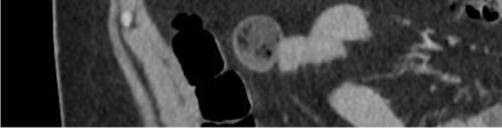

A31-year-oldobese,Hispanicmalepresentedtothe emergencydepartmentwithprogressivelyworseningleft upperquadrantabdominalpainfor fivedays.Thepainwas describedascramping,intermittent,andexacerbatedby bendingforward.Hedeniedpastmedicalhistory. Severaldayspriortopresentationthepatienthadbeen evaluatedbyhisprimarycarephysician.Hewasdiagnosed withmusculoskeletalpainandprescribedcyclobenzaprine. Sincetheevaluationbytheprimarycarephysician,thepain hadincreasedinfrequencyandintensity.Thepatientdenied anynausea,vomiting,fevers,diarrhea,orhematochezia.He did,however,reportintentionalweightlossof15kilograms. Tenweeksprior,thepatienthadingestedanIGB(Allurion,

formerlyknownasElipse),forweight-losspurposesunder thecareofaphysicianinJuárez,Mexico.

Oninitialevaluation,vitalsignswerenormalexceptfor sinustachycardiaat105beatsperminute.Hewasinmild distresswithmoderatetendernesstopalpationintheleftupper quadrant.Therewasnoguarding,rebound,orrigidity. Laboratoryevaluationshowedawhitebloodcellcountof 21.7 × 103 cellspercubicmillimeter(mm3)(referencerange 4.5 11 × 103 cells/mm3)withaneutrophilpredominanceof 18.9 × 103 cells/mm3 (2 7.8 × 103 cells/mm3)andanelevated bloodureanitrogenat25milligrams(mg)/deciliter(dL) (9–20mg/dL).Thepatient’selectrolytes,liverfunction tests,andserumcreatininewerewithinnormallimits. Acomputedtomography(CT)oftheabdomenandpelviswith intravenouscontrastwasorderedtoassessforbowel obstruction,perforation,andballoonintegrity.TheCT indicatedintraluminalgastricballoonwithanteriorgastricwall perforationwithoutevidenceofintestinalpathology(Image).

GeneralsurgerywasconsultedandobtainedaCT abdomenandpelviswithoralcontrast,whichdirectly showedextravasationintotheperitonealcavity.Thepatient wasemergentlytakentotheoperatingroomforan exploratorylaparotomy,abdominalwashout,removalofthe IGB,andgastricperforationrepair.Hewasstartedon piperacillin/tazobactamand fluconazoleforpurulent peritonitis.Afteranovernightstayinthesurgicalintensive careunit,hewastransferredtothesurgical floorwherehe remainedforthefollowing10days.Onday5,afollow-up uppergastrointestinalserieswithgastrografinwasobtained, andnocontrastextravasationwasnoted.Thepatient’sdiet wasadvanced,andhewasdischargedonpostoperativeday 10withamoxicillin-clavulanatefor10days.Forty-twodays afterdischargethepatientwasnotedtoberecoveringwellon afollowupvisit.